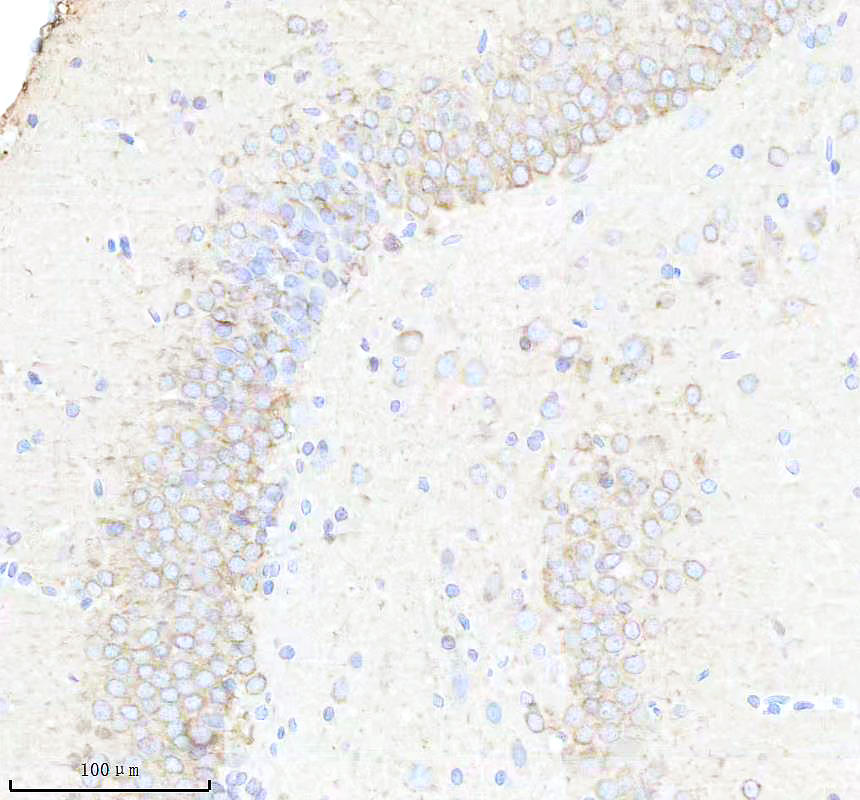

IHC analysis of BNIP3L using anti-BNIP3L antibody (BM5174) .

BNIP3L was detected in a paraffin-embedded section of rat hippocampus tissue. The tissue section was incubated with rabbit anti-BNIP3L Antibody (BM5174) at a dilution of 1:200 and developed using HRP Conjugated Rabbit IgG Super Vision Assay Kit (Catalog # SV0002) with DAB (Catalog # AR1027) as the chromogen.

IHC analysis of BNIP3L using anti-BNIP3L antibody (BM5174) .

BNIP3L was detected in a paraffin-embedded section of rat hippocampus tissue. The tissue section was incubated with rabbit anti-BNIP3L Antibody (BM5174) at a dilution of 1:200 and developed using HRP Conjugated Rabbit IgG Super Vision Assay Kit (Catalog # SV0002) with DAB (Catalog # AR1027) as the chromogen.